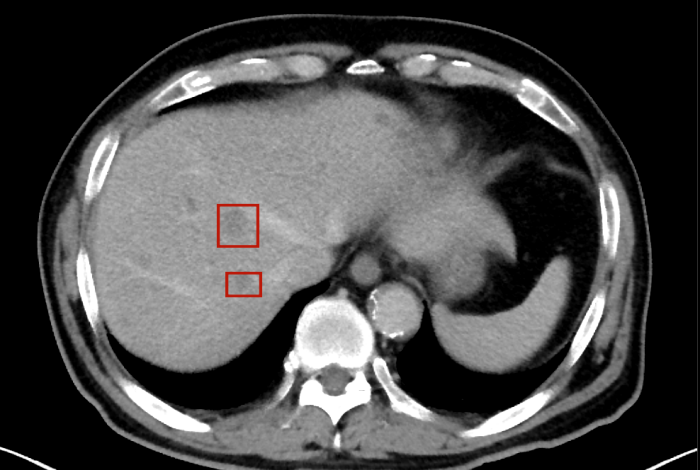

術(shù)后,萬秀萍為黃先生做進(jìn)一步的檢查,腹部磁共振(MRI)檢查顯示:肝臟區(qū)域出現(xiàn)了轉(zhuǎn)移病灶的陰影。

在腫瘤治療領(lǐng)域,一旦出現(xiàn)遠(yuǎn)處器官(如肝臟)轉(zhuǎn)移,通常意味著疾病進(jìn)入晚期階段。 肝膽外科專家會診后也給出了“目前無法通過手術(shù)達(dá)到根治”的結(jié)論。這個診斷,像一塊沉重的巨石,壓在了黃先生和家人的心頭。

轉(zhuǎn)移病灶的陰影

目前,黃先生的腫瘤活動已得到有效抑制,肝臟轉(zhuǎn)移灶未見爆發(fā)性進(jìn)展,病情整體保持穩(wěn)定。